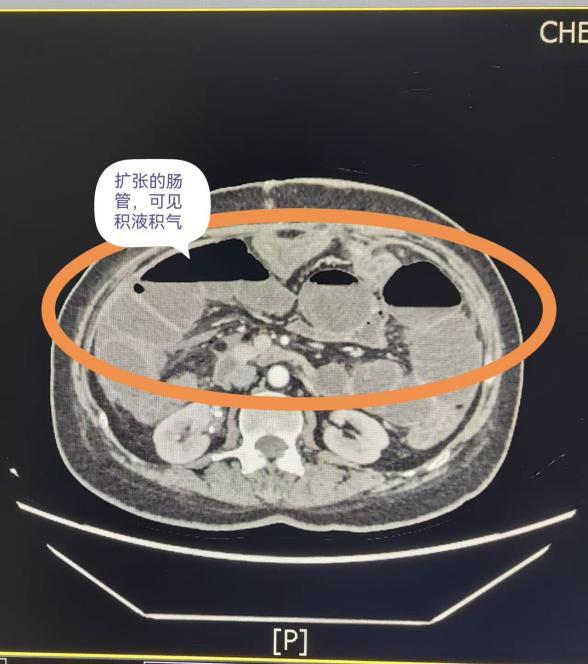

明显扩张的肠管

如何让谢女士在梗阻没解除的情况下,还能从嘴里吃点东西呢?成都市第五人民医院普通外科内镜外科组提出了一个关键方案——肠梗阻导管置入术。

导管下降过程中,梗阻可见缓解

在无痛胃镜的引导下,医生从谢女士鼻腔放入一根细长的导管,慢慢送到十二指肠。随着肠道自己的蠕动,管子不断往下走,最后到达堵塞位置的上方。这根管子能把堵住那段肠子里积存的液体和气体引出来,让腹胀的感觉减轻。同时,也因为有了这条通路,谢女士才能重新尝试从嘴里进食。

术后,谢女士的肚子没那么胀了,消化液被顺利引流出,她也慢慢开始能吃东西了。后来医生通过导管造影检查,更清楚地看到了堵塞的位置和程度,这对之后的治疗很有帮助。